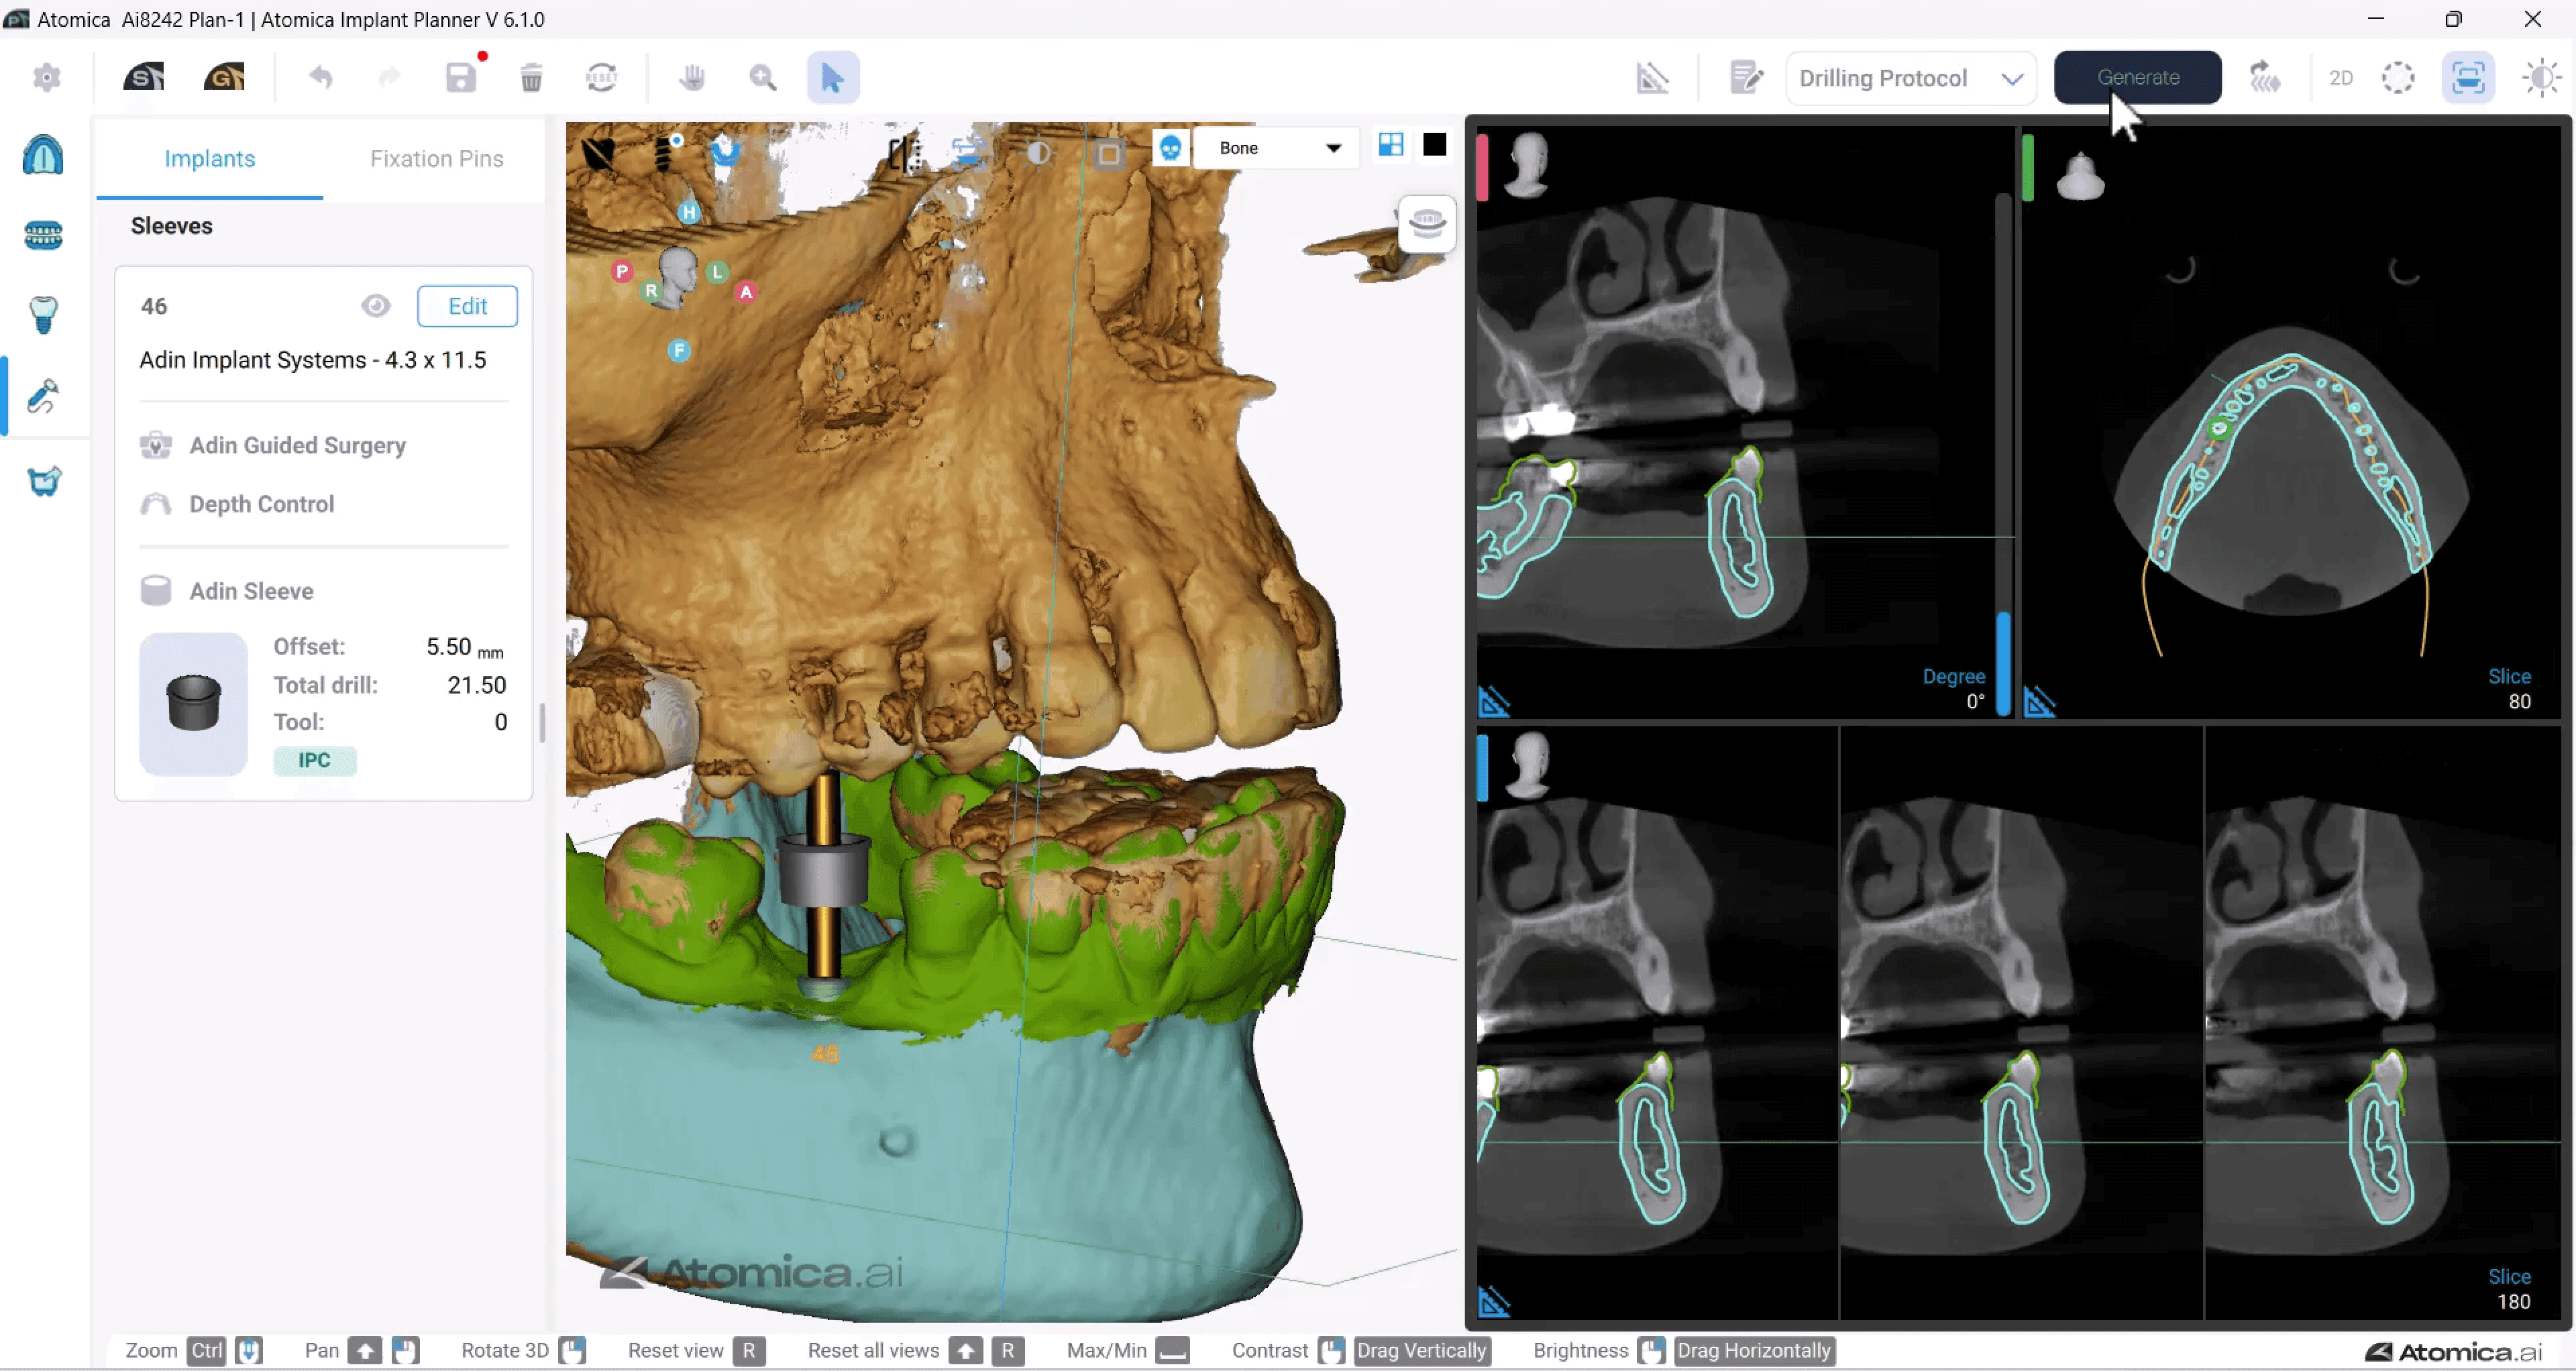

Seamless digital solutions for every step of the implant journey.

From scan to final delivery, 3Sixty streamlines your workflow with smart planning, precision guides, and real clinical support.

3Sixty is a digital dental lab with 150+ dental and technical experts supporting every case. From treatment planning to surgical guides and full-arch workflows like our groundbreaking Anatomic Guide®, we help streamline complex procedures. Trusted by over 3,000 dentists, we make digital implant dentistry simpler, faster, and more predictable.